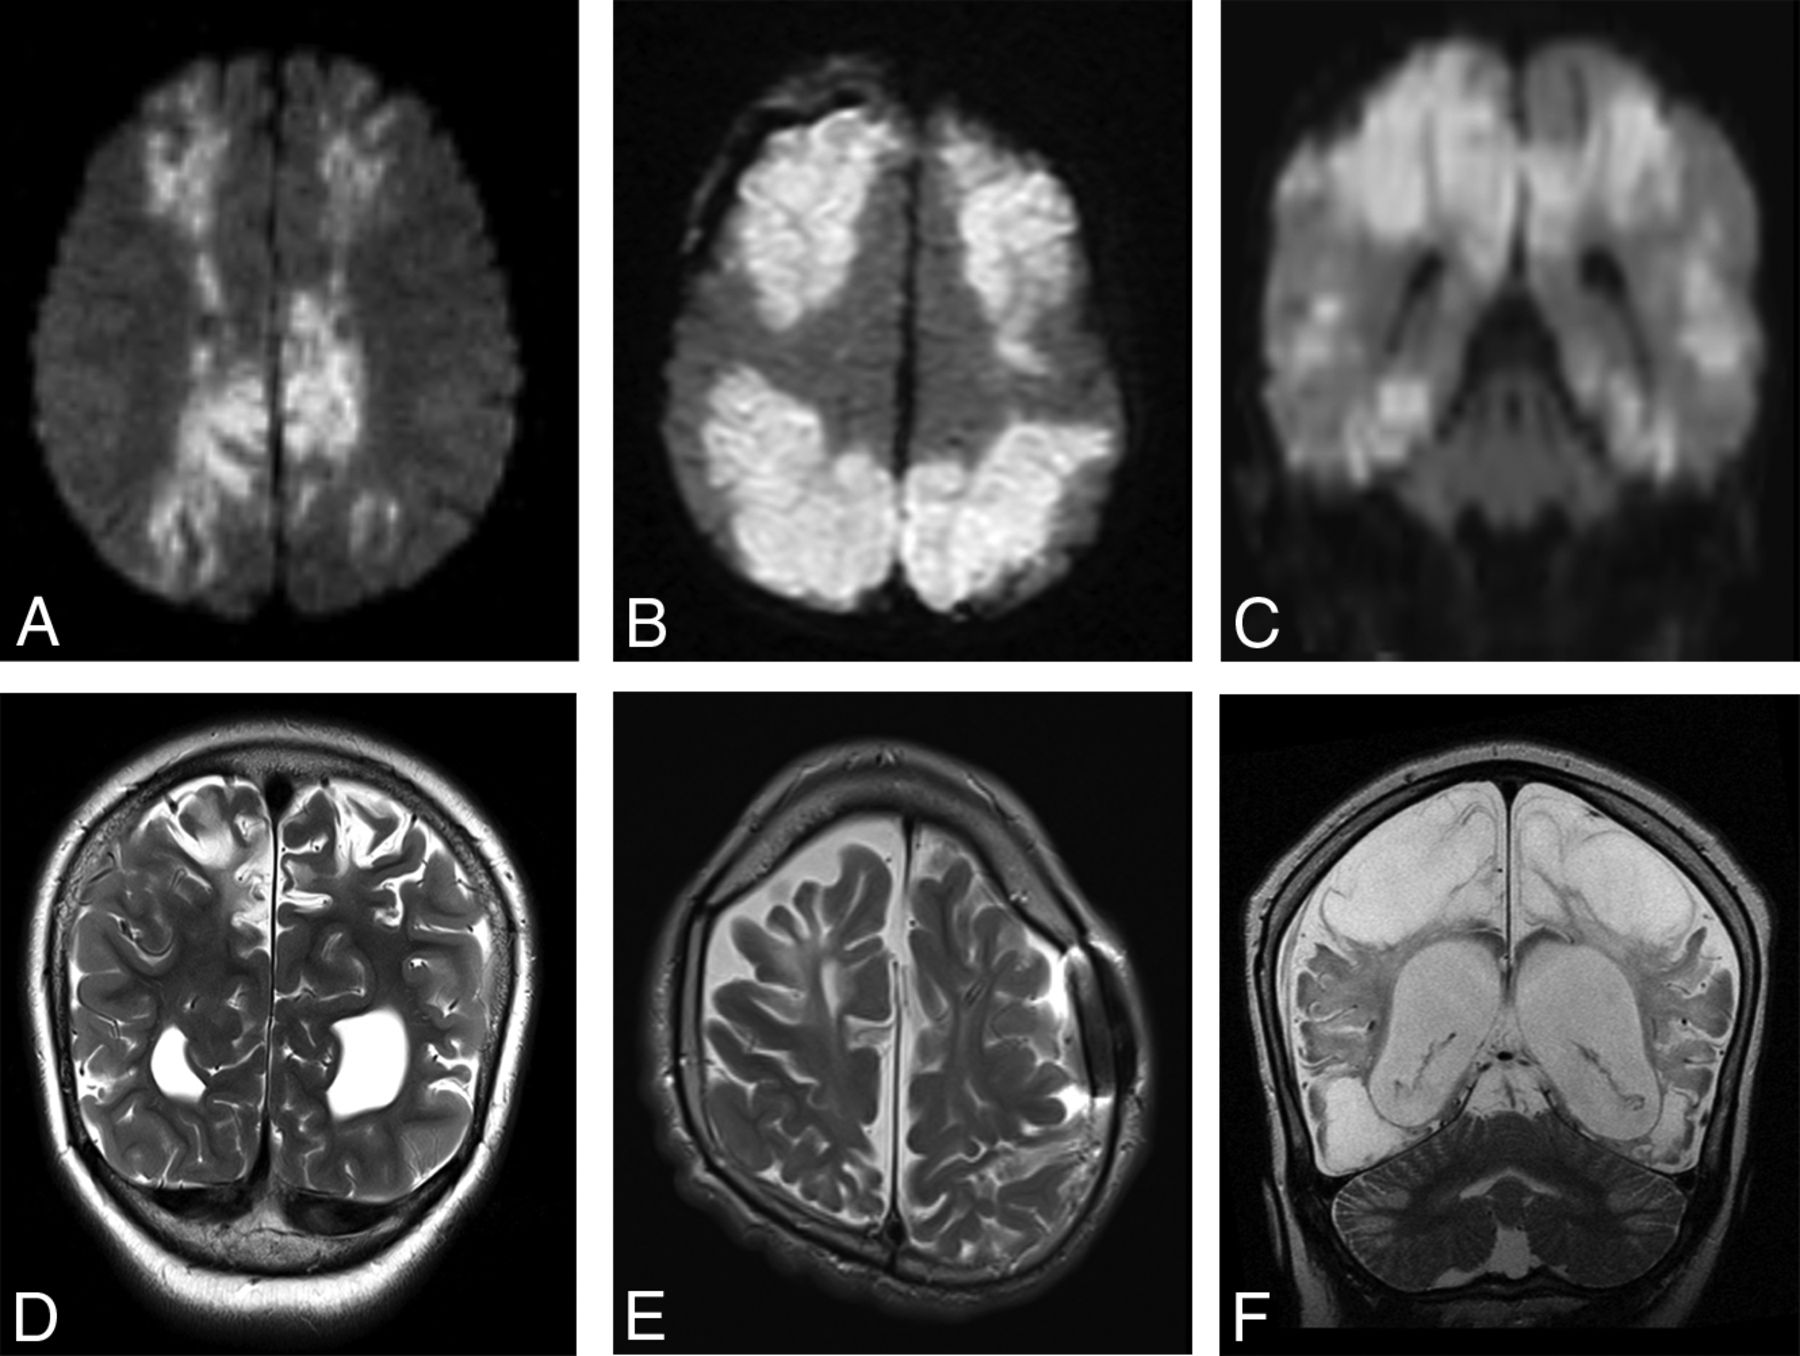

Imaging was available for 16/23 patients during the acute phase of injury, defined as <7 days from the suspected clinical event. All patients demonstrated normal thickness or a mildly thickened cerebellar cortex (Figs 3 and 4). Eighty-one percent (13/16) of patients demonstrated acute diffusion restriction (12 with an eventual clinical diagnosis of HII, 1 of unknown etiology) (Fig 4A–C), while 19% (3/16) of patients demonstrated no diffusion abnormality (all with an eventual clinical diagnosis of PRES) (Fig 4D–F). The 3 patients with PRES were imaged in the acute phase only, with no imaging follow-up available.

Coronal T2WI (A), coronal DWI (B), and coronal ADC map (C) from patient 18 demonstrate acute cerebellar and supratentorial injury with T2 prolongation and restricted diffusion in the setting of HII. Coronal T2WI (D), coronal DWI (E), and coronal ADC map (F) from patient 9 demonstrate acute cerebellar (white arrowheads) and supratentorial (white arrows) injury without diffusion restriction in the setting of PRES.

In the supratentorial brain, 87% (20/23) of patients demonstrated a classic parasagittal watershed pattern of cortical injury (Fig 7), with 11 with additional evidence of associated basal ganglia injury. Seventeen patients had watershed infarctions and a concordant clinical history of HII. The remaining 3 patients demonstrated a watershed pattern of injury typical of PRES. In all cases, the apparent timing of the supratentorial injury was consistent with the estimated timing relative to the suspected clinical event.

Findings of both acute and remote supratentorial watershed injury in patients 1–6 (A–F, respectively). Acute watershed infarcts with signal abnormality on axial (A and B) and coronal (C) DWI in a characteristic parasagittal distribution. Subacute or remote watershed infarcts with hyperintensity and parenchymal volume loss on coronal (D and F) and axial (E) T2.